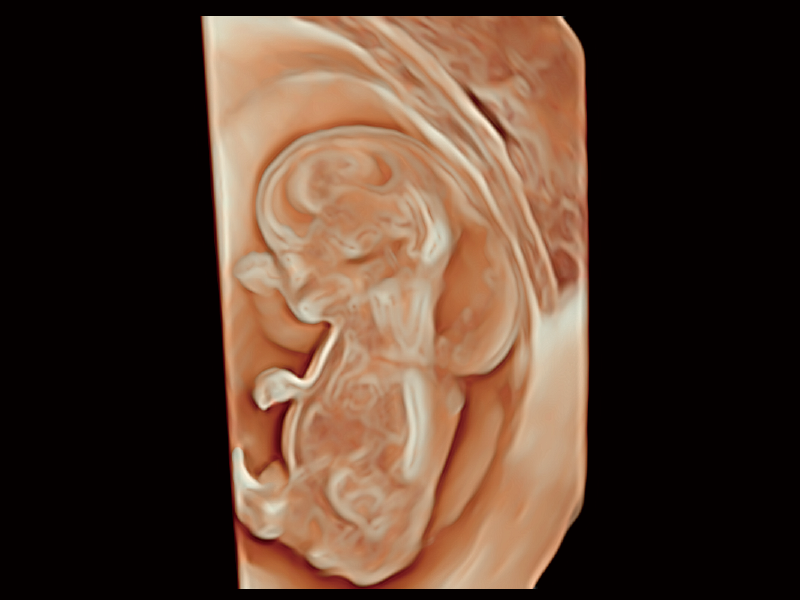

睿顏成像

S-Fetus? 鳳眼

胎兒顱腦融合